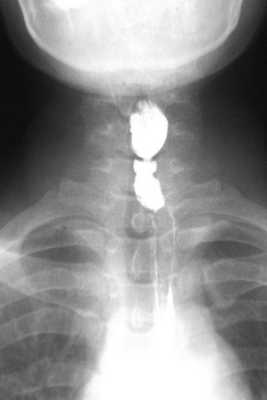

Больная Р., 48 лет, госпитализирована с жалобами на затруднение прохождения твердой и жидкой пищи по пищеводу, чувство тяжести за грудиной, ощущение застревания пищевого комка в области шеи, выраженную слабость, приступы сердцебиения, осиплость голоса, одышку при физической нагрузке. В 2006 г. при плановом обследовании была диагностирована железодефицитная анемия, гемоглобин 75 г/л. Проведенная тогда же ЭГДС позволила выявить лишь признаки хронического атрофического гастрита. С этого момента пациентка самостоятельно бессистемно принимала препараты железа без выраженного эффекта. Признаки дисфагии впервые появились лишь спустя 3 года, однако за медицинской помощью больная обратилась лишь в июне 2011 г. В анализах крови была выявлена хроническая гипохромная железодефицитная анемия (гемоглобин 77,9 г/л, цветовой показатель 0,49, гематокритное число 26,62%, средний объем клетки 56,3 мкм 3 ) и сидеропения (железо 4,3 мкмоль/л, насыщение железом 5,5%, ферритин 3 мкг/л, трансферрин 3,07 г/л). Полипозиционная рентгенография: в шейном отделе пищевода на уровне C6 участок циркулярного сужения протяженностью около 1-2 мм и диаметром до 3 мм (рис. 1). Рисунок 1. Рентгенограммы. а - короткая мембранозная стриктура шейного отдела пищевода больной Р., 48 лет. Рисунок 1. Рентгенограммы. б - баллонная дилатация стриктуры до полного расправления диаметром 2 см. Рисунок 1. Рентгенограммы. в - после дилатации. После приема густой взвеси бария явного супрастенотического расширения не выявлено. ЭГДС: устье пищевода проходимо, в шейном отделе пищевода просвет сужен до 2-3 мм, для аппарата непроходим. Выполнено два сеанса баллонной дилатации стриктуры под контролем рентгенотелевидения до максимального диаметра 2 см. Восполнен дефицит железа (космофер, ферлатум), уровень гемоглобина поднялся до 118 г/л.

Больная Я., 39 лет, госпитализирована с аналогичными жалобами, среди которых превалировала дисфагия. В 2004 г. впервые обратила внимание на чувство дискомфорта и инородного тела в горле во время приема пищи, однако за медицинской помощью не обратилась. В течение последующих 5 лет клиническая картина нарастала: появилась выраженная слабость, быстрая утомляемость, прогрессировала дисфагия вплоть до затруднения прохождения жидкой пищи по пищеводу. Госпитализирована в хирургическое отделение, где при рентгенографии была выявлена короткая стриктура шейного отдела пищевода (рис. 2). Рисунок 2. Рентгенограмма. Короткая мембранозная стриктура шейного отдела пищевода больной Я., 39 лет. Общий анализ крови: гемоглобин 42,0 г/л, цветовой показатель 0,45, сидеропения (железо 10 мкг/дл, насыщение железом 2,1%). ЭГДС: устье пищевода проходимо, в шейном отделе пищевода просвет сужен до 3-4 мм, для аппарата непроходим, ткани в этом отделе рубцово изменены. Лечение начато с переливания эритроцитной массы. Последовательное применение препаратов железа (космофер, ферлатум, венофер, ферофольгамма) позволило поднять уровень гемоглобина крови до 115 г/л. Проведение трех сеансов баллонной дилатации стриктуры под контролем рентгенотелевидения до максимального расправления баллона (2 см) позволило ликвидировать стриктуру и проявления дисфагии.